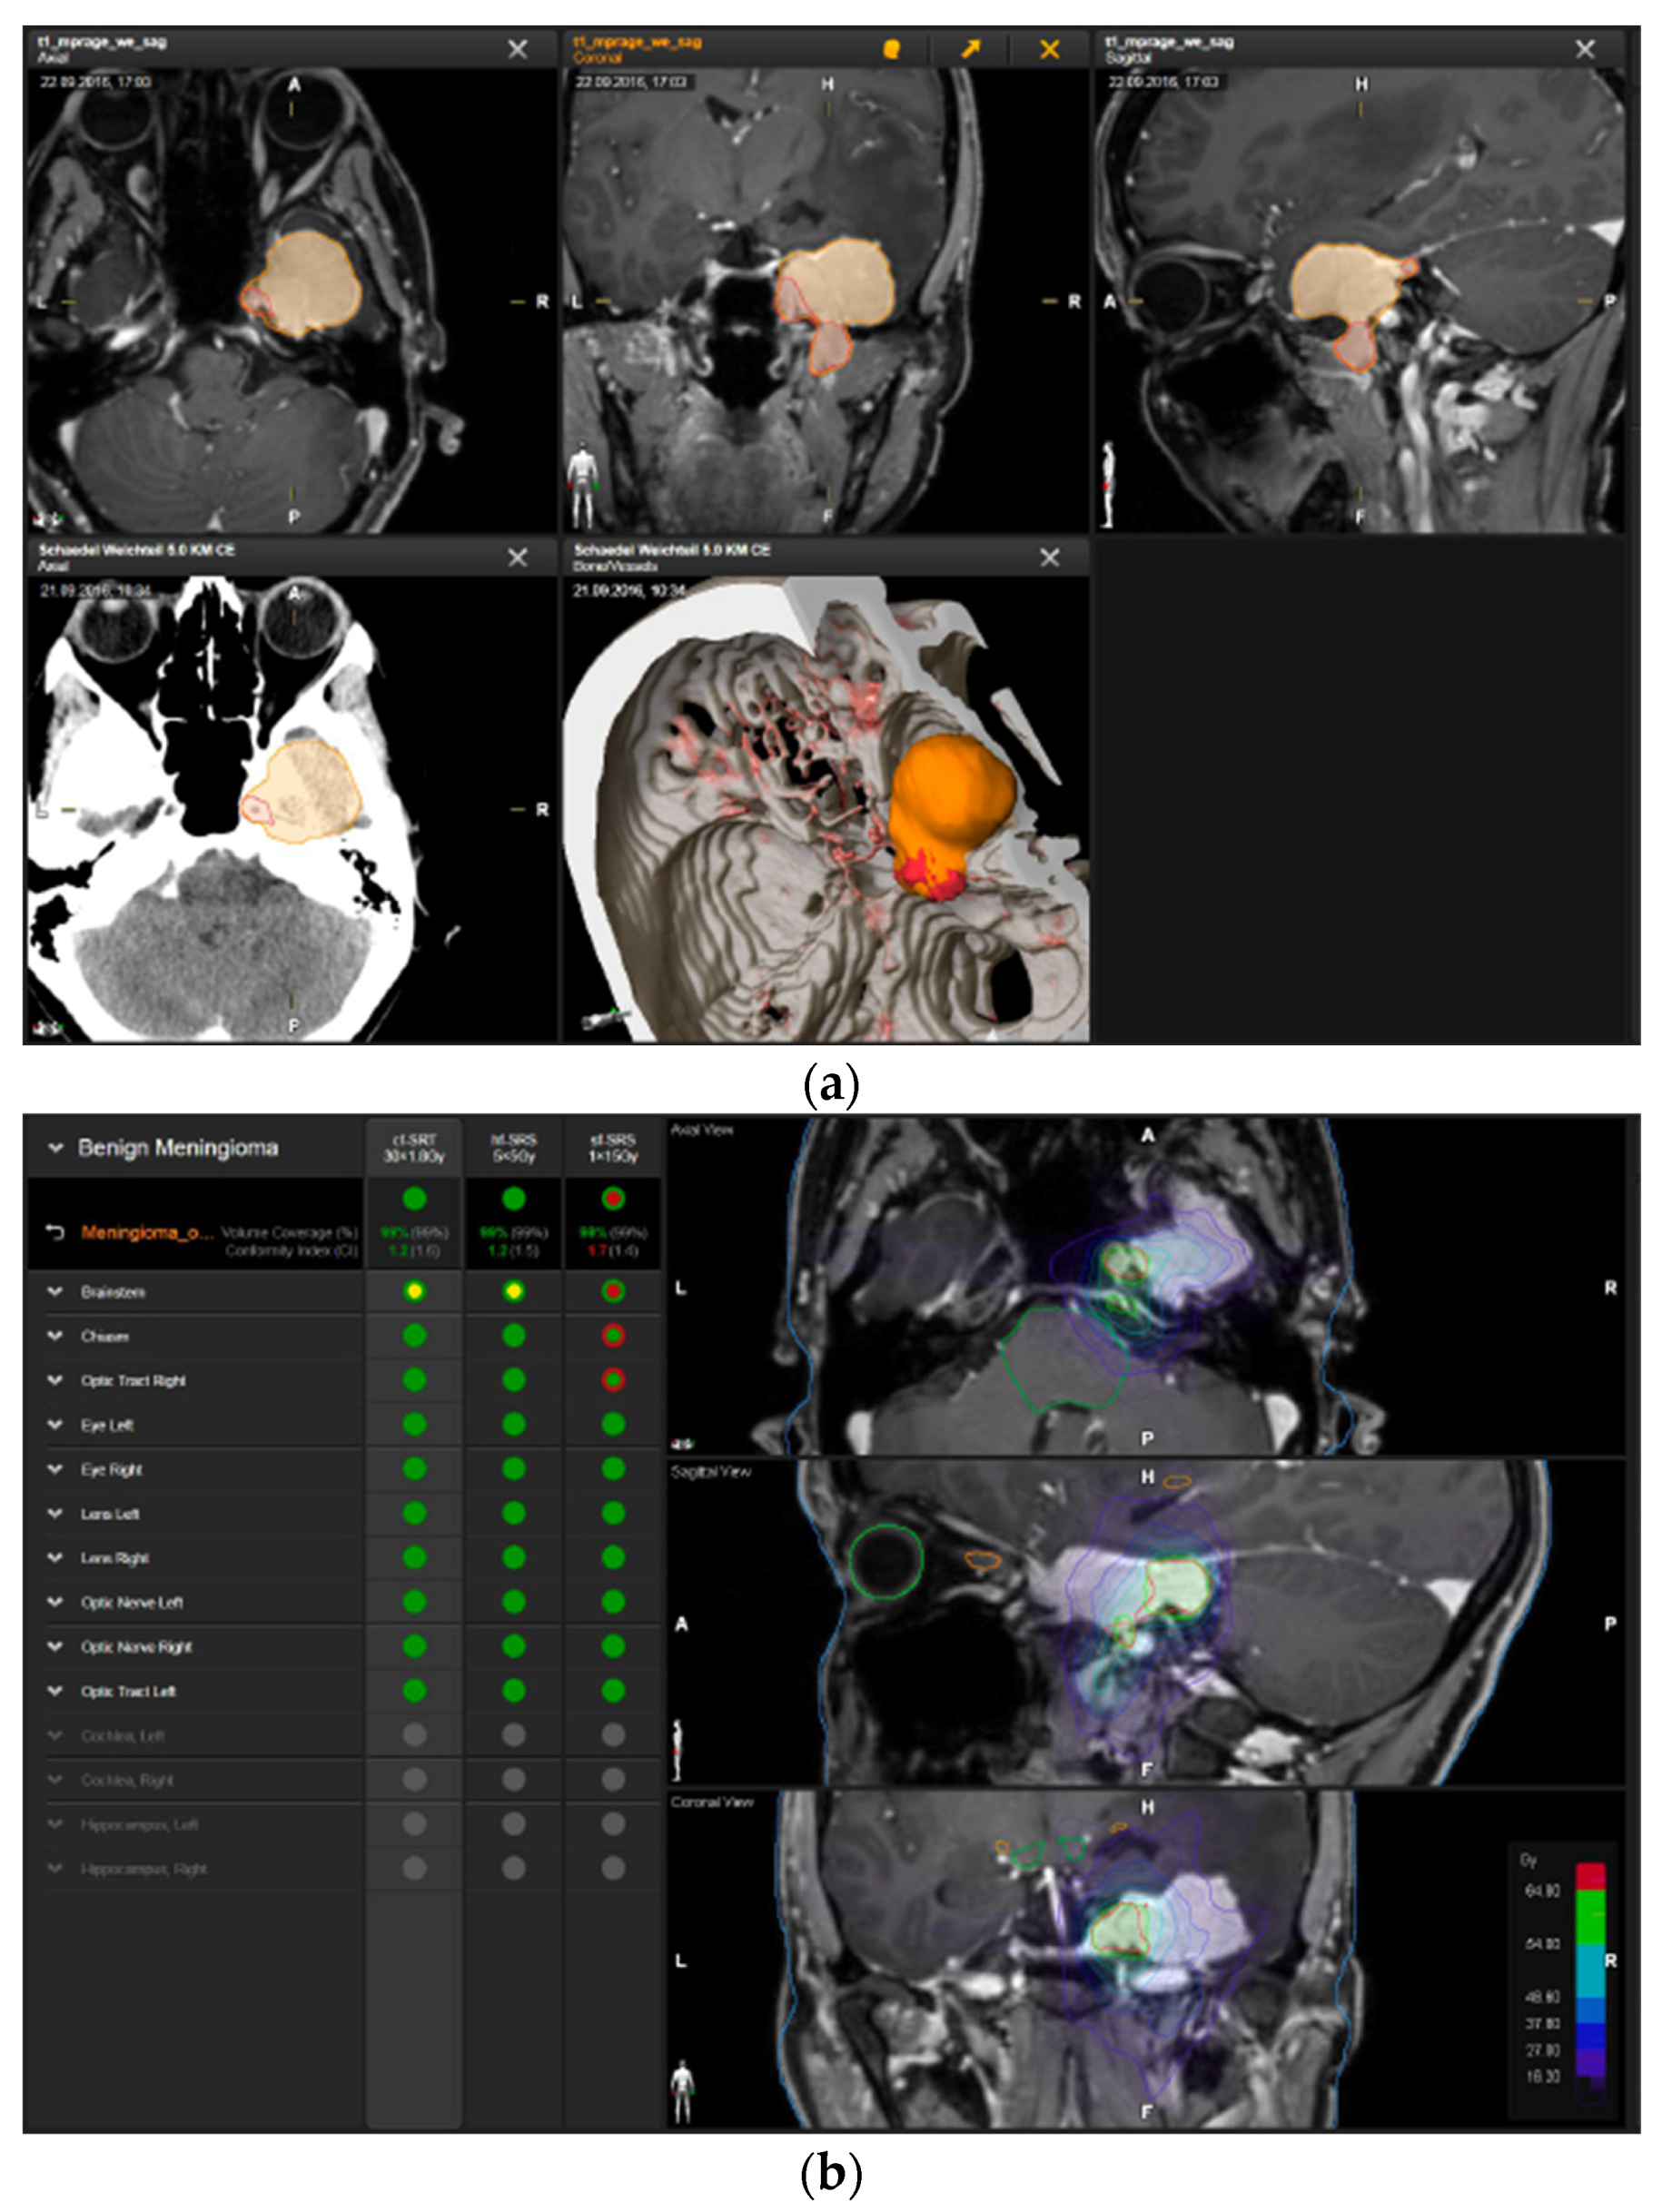

A 58-year-old female presented with progressive headache, difficulty swallowing, diplopia, hearing loss, and reduced face sensitivity on the right side (Figure 4). Elective craniotomy and AHSA-assisted tumor resection were performed. The patient underwent hypofractionated radiosurgery (5 × 5 Gy) of the residual meningioma one year after tumor resection.

Figure 4.

Second representative case of AHSA-supported tumor resection. (a) MRI imaging of petroclival meningioma (axial, coronal, sagittal). (b) Depiction of preoperative tumor volume (orange) and planned residual tumor volume (red). (c) AHSA summary table showing the stereotactic radiation constraints for the preoperatively planned residual tumor volume. With this plan, conventional fractionation and hypofractionation were feasible with effective tumor coverage.

—brainstem: mean dose is safe, while the max. dose is marginally safe;

—right optic tract: mean dose unsafe, max. dose is marginally safe;

—right hippocampus: marginally safe, and mean dose unsafe, max. dose is marginally safe. (d) First intraoperative structure update (ISU) with a residual tumor volume of 82% with the calculated dose constraints for conventional and hypofractionated radiotherapy. Single dose stereotactic radiosurgery was not feasible with this degree of remaining tumor. At this point, the dose constraints for conventional radiotherapy were: